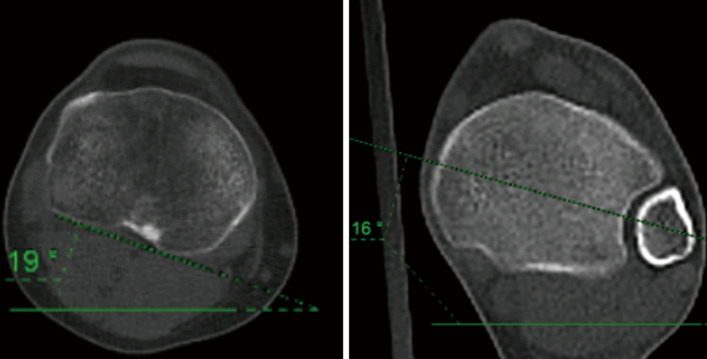

Key content and findings: Computed tomography (CT) is still considered the best method to measure both femoral and tibial torsional angles. Its main limitation, the radiation exposure, has been recently addressed with ultra-low dose protocols that were proven to be as accurate as standard protocols. On the other hand, magnetic resonance imaging (MRI) offers a nonionizing, radiation-free option that is now considered almost equivalent to CT. However, MRI consists in a long and expensive procedure that can be hindered by issues linked to metal implants, patient's positioning and measurement variabilities. Lastly, three-dimensional (3D) reconstructions derived from low-dose biplanar radiographies (LD-BRs) have been proposed as a low-radiating, quick and reliable solution to overcome the limitations of both MRI and CT scans.